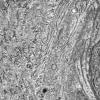

VASCULAR

Hypoxia-Ischemia, fetal-neonatal

White Matter (12)